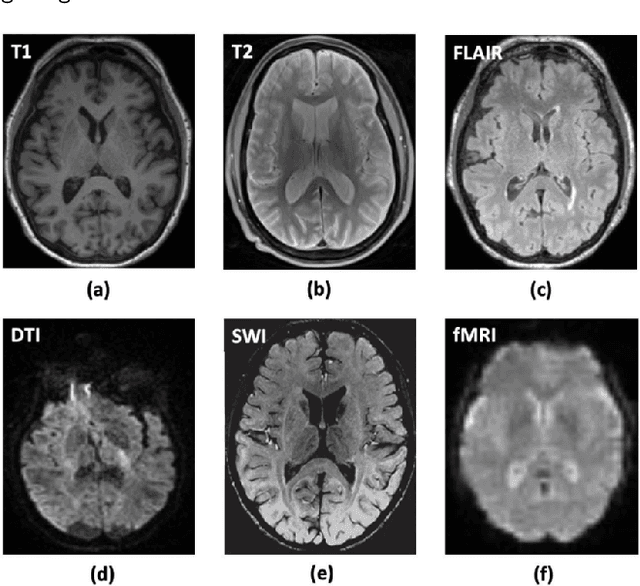

Abstract:Medical imaging is essential in healthcare to provide key insights into patient anatomy and pathology, aiding in diagnosis and treatment. Non-invasive techniques such as X-ray, Magnetic Resonance Imaging (MRI), Computed Tomography (CT), and Ultrasound (US), capture detailed images of organs, tissues, and abnormalities. Effective analysis of these images requires precise segmentation to delineate regions of interest (ROI), such as organs or lesions. Traditional segmentation methods, relying on manual feature-extraction, are labor-intensive and vary across experts. Recent advancements in Artificial Intelligence (AI) and Deep Learning (DL), particularly convolutional models such as U-Net and its variants (U-Net++ and U-Net 3+), have transformed medical image segmentation (MIS) by automating the process and enhancing accuracy. These models enable efficient, precise pixel-wise classification across various imaging modalities, overcoming the limitations of manual segmentation. This review explores various medical imaging techniques, examines the U-Net architectures and their adaptations, and discusses their application across different modalities. It also identifies common challenges in MIS and proposes potential solutions.